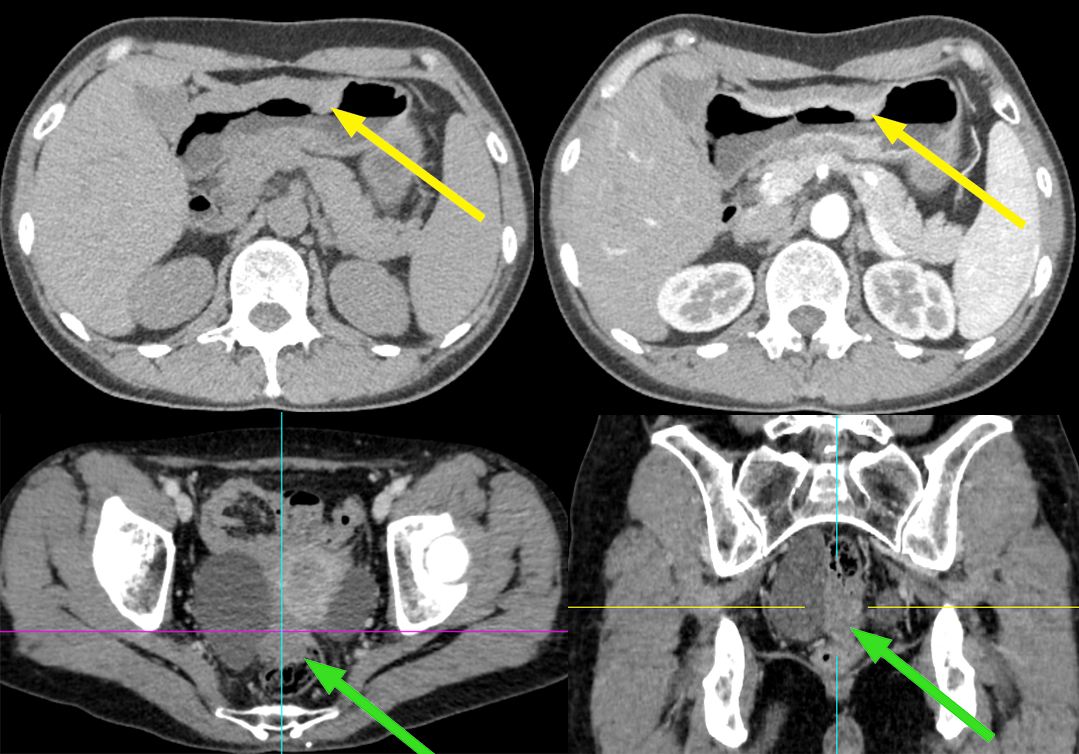

患者,女,51 岁,因上腹部不适 1 年,加重伴黑便 10 天 入院,胃镜及病理考虑胃粘液腺癌;CA125 正常。

影像描述:胃腔充盈尚可,贲门、胃小弯、胃体下部、胃角壁弥漫性增厚,不均匀明显强化,胃小弯侧浆膜层毛糙,周围脂肪间隙略浑浊,见结节样软组织影,大小约 0.8-1.0 cm,轻度强化。右侧附件区见团块状囊实混杂密度影,可见强化,与直肠分界不清。

患者,女,70 岁,因排便习惯改变 1 年入院,肠镜及病理:升结肠近回盲部中低分化腺癌;CA125 正常。

影像描述:回盲部肠壁限局性环状增厚,突向腔内,表面不光滑,管腔明显变窄,浆膜层毛糙,增强呈明显不均匀强化,与肠壁边界不清,与周围组织分界尚清,周围脂肪间隙密度增高、浑浊,可见多个结节状软组织密度影,大小约 0.4-1.3 cm,明显强化。右侧附件区见较大囊实性团块影,其内可见分隔,大小约 6.7X5.5 cm,增强扫描实性部分及分隔可见明显强化,与邻近肠管及子宫体分界略欠清。

病例 1 手术:胃腺癌合并卵巢转移癌

病例 2 手术:结肠癌合并卵巢转移癌

3、卵巢转移瘤 CT 表现:CT 是鉴别诊断的重要手段,双侧或单侧卵巢实性(乳腺癌,小)或囊实性(结肠癌,大)肿块,80% 的卵巢转移瘤为双侧生长,密度不均,大小不等,常有大量腹水和其他部位转移。